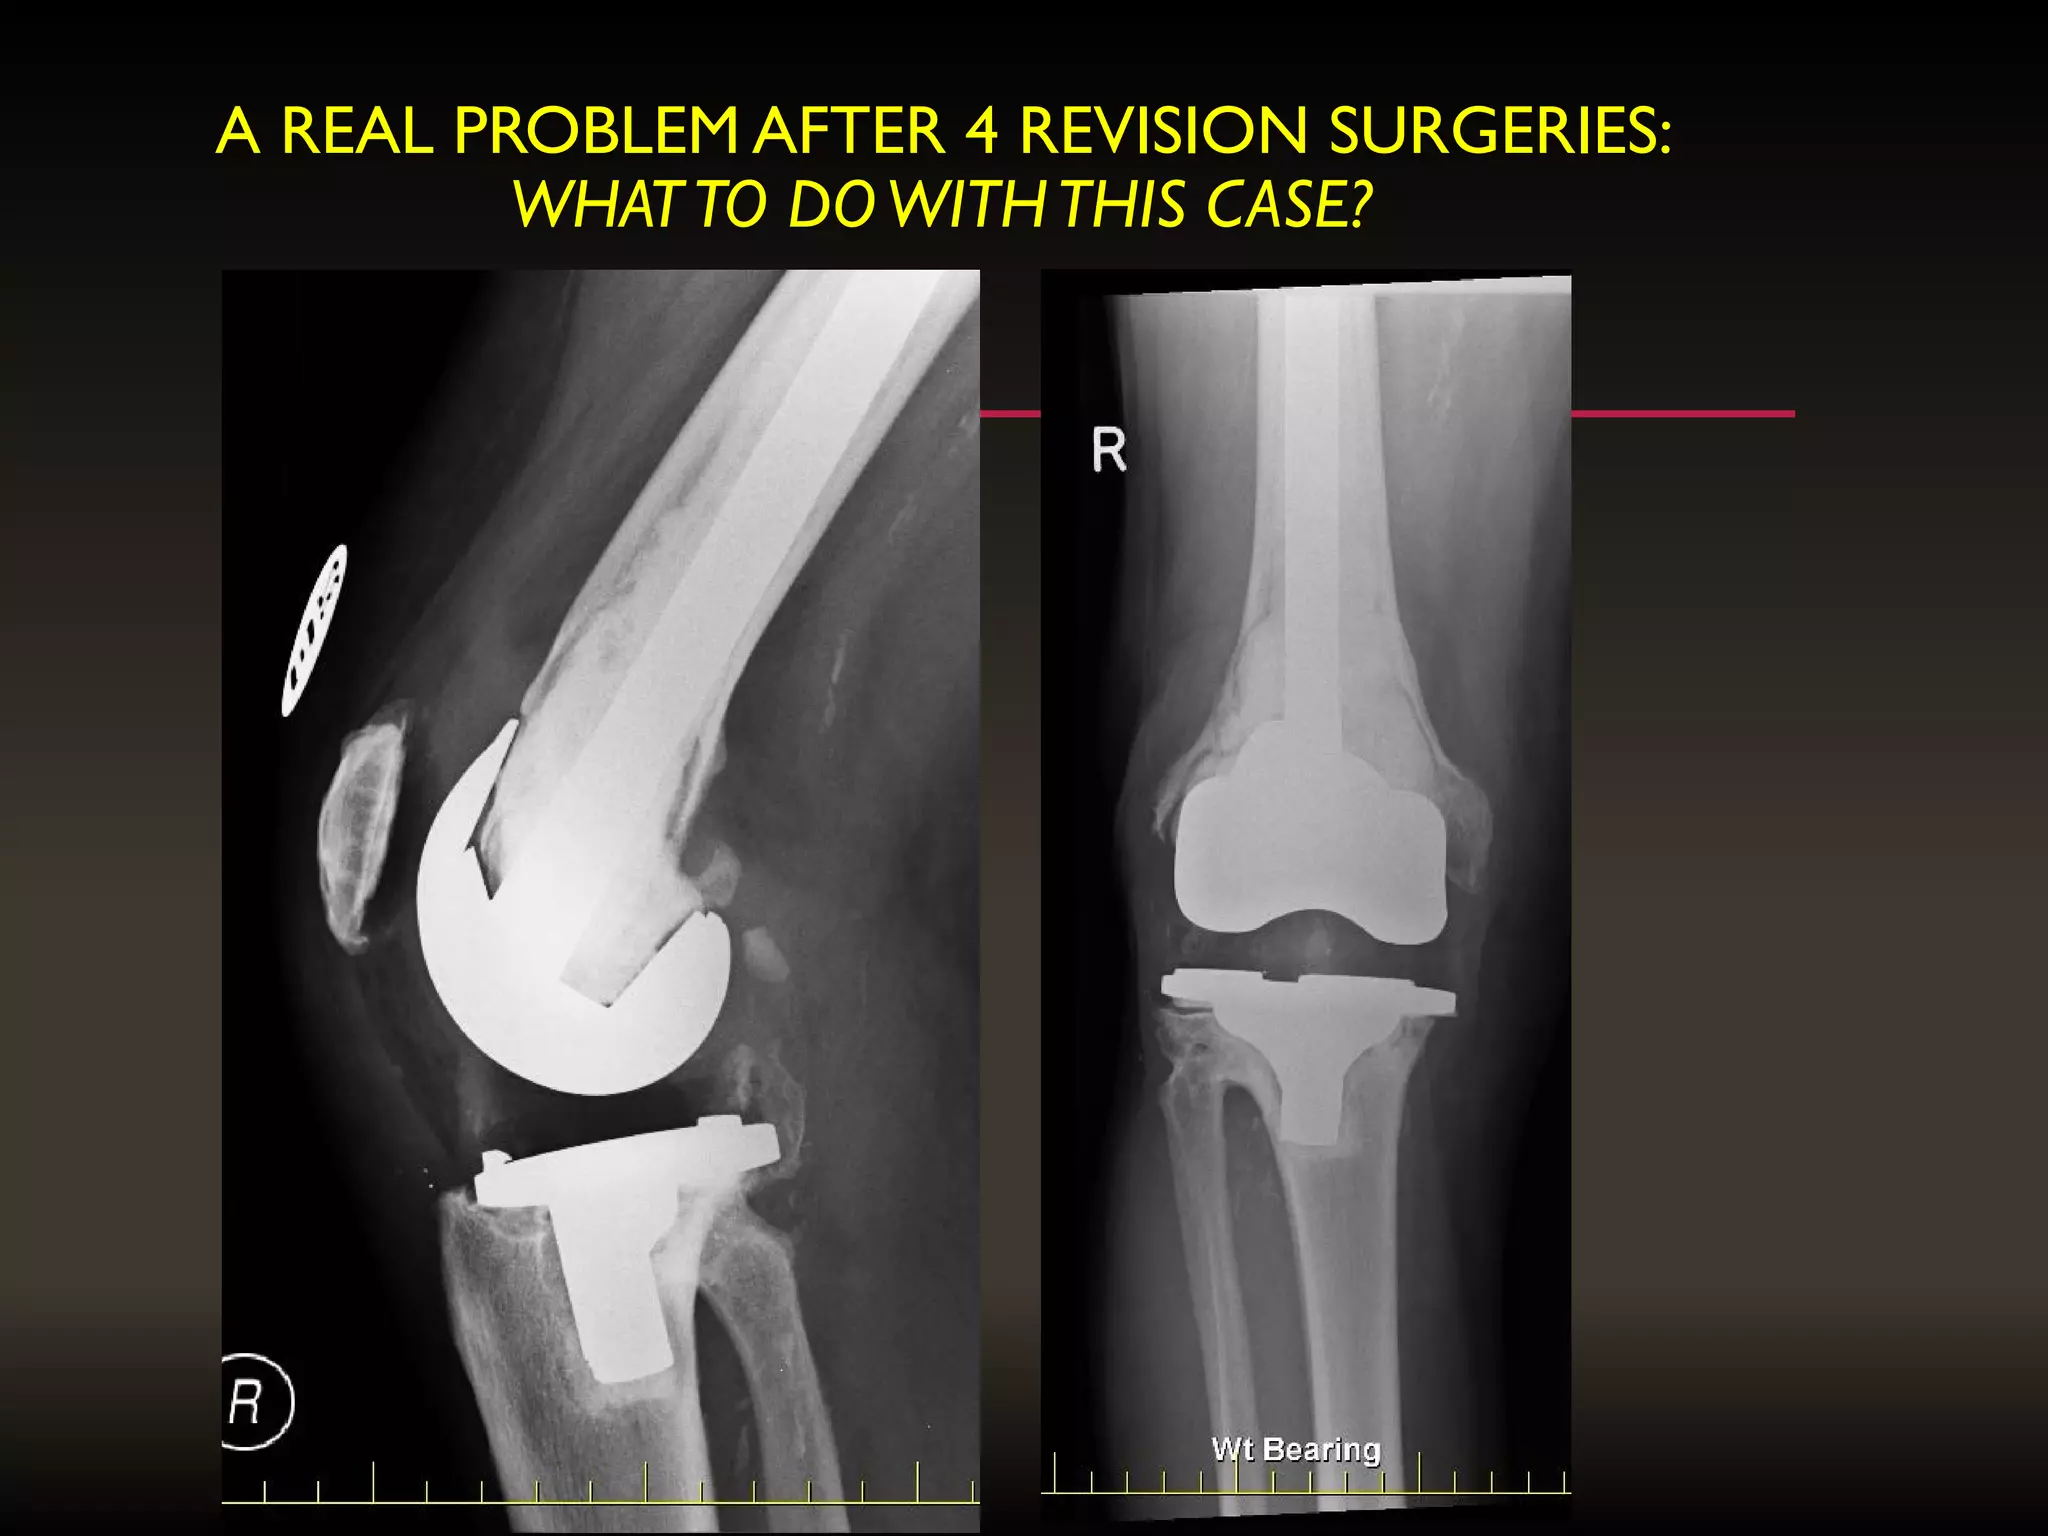

A REAL PROBLEM AFTER 4 REVISION SURGERIES:

WHATTO DOWITHTHIS CASE?

A REAL PROBLEMAFTER 4 REVISION SURGERIES: WHATTO DOWITHTHIS CASE?